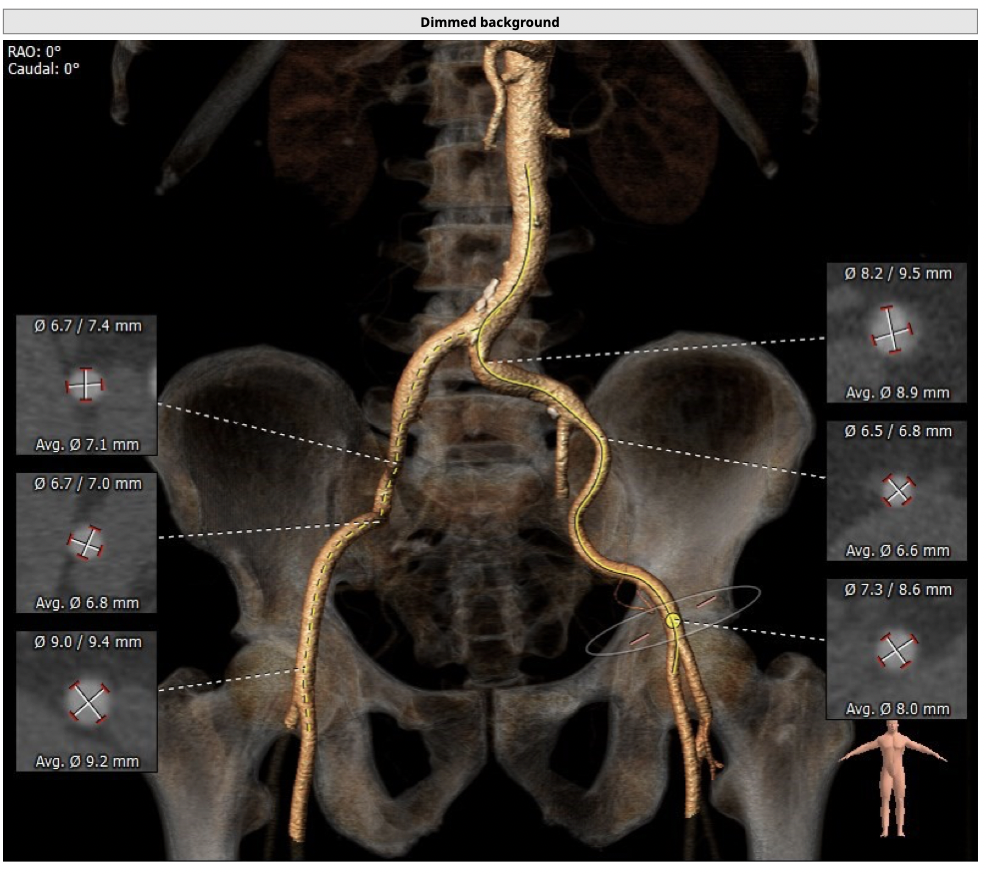

主动脉CT

*功能型二叶瓣,瓣叶增厚,重度钙化,瓣环及左室流出道层面仍可见钙化,左右可见钙化融合,瓣膜释放后发生瓣周漏的风险较高,瓣膜释放后容易移位。

*左右股动脉较细,直径小于6mm, 双侧髂动脉-股动脉走形迂曲,可见明显钙化,术中操作需谨慎轻柔,注意血管并发症的发生。

*左室腔较大,术中需注意液体管理。

经分析研判,拟从右侧股动脉穿刺入路,使用22mm球囊预扩,选用L26号的VenusA-Valve瓣膜,采用VenusA-Plus可回收输送系统进一步确保手术安全,瓣膜释放后结合造影和超声情况,决定是否后扩。